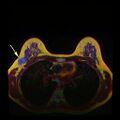

يشير فحص سرطان الثدي إلى اختبار النساء اللائي يتمتعن بصحة جيدة لسرطان الثدي في محاولة لتحقيق تشخيص مبكر على افتراض أن الاكتشاف المبكر سيحسن النتائج. تم استخدام عدد من اختبارات الفحص بما في ذلك الفحص السريري والذاتي فحوصات الثدي وتصوير الثدي والفحص الجيني والموجات فوق الصوتية والتصوير بالرنين المغناطيسي.

يتضمن الفحص السريري أو الذاتي للثدي تحسس الثدي للوقوف على وجود كتل أو أي تشوهات أخرى. يتم إجراء فحوصات الثدي السريرية من قبل مقدمي الرعاية الصحية، بينما تُجرى فحوصات الثدي الذاتية من قبل الشخص نفسه.[109] لا تدعم الأدلة فعالية أي من نوعي فحوصات الثدي، لأنه بحلول الوقت الذي يصبح فيه الورم كبيرًا بما يكفي ليتم اكتشافه، من المحتمل أن ينمو لعدة سنوات وبالتالي يصبح كبيرًا بما يكفي ليتم لاكتشافه بدون فحص.[110][111] يستخدم فحص التصوير الإشعاعي لسرطان الثدي بالأشعة السينية لفحص الثدي بحثًا عن أي كتل. أثناء الفحص، يتم ضغط الثدي ويلتقط الفني صورًا من زوايا متعددة. يلتقط التصوير الشعاعي للثدي العام صورًا للثدي بأكمله، بينما يركز تصوير الثدي الشعاعي التشخيصي على كتلة معينة أو منطقة معينة مثيرة للقلق.[112]

ينص تعاون كوكرين (2013) على أن أفضل دليل جودة لا يوضح انخفاضًا في سرطان محدد، ولا انخفاض في جميع أسباب الوفيات الناتجة عن فحص التصوير الشعاعي للثدي.[9] عند إضافة تجارب أقل صرامة إلى التحليل، يحدث انخفاض في معدل الوفيات بسبب سرطان الثدي بنسبة 0.05% (انخفاض 1 كل 2000 حالة وفاة بسبب سرطان الثدي على مدى 10 سنوات أو انخفاض نسبي بنسبة 15% للوفيات بسبب سرطان الثدي).[9] يؤدي الفحص على مدى 10 سنوات إلى زيادة بنسبة 30% في معدلات الإفراط في التشخيص والعلاج الزائد (3 إلى 14 لكل 1000) وأكثر من نصفهم سيحصلون على اختبار واحد إيجابي كاذب على الأقل.[9][118] وقد أدى ذلك إلى الرأي القائل بأنه ليس من الواضح ما إذا كان فحص التصوير الإشعاعي للثدي يفيد أم يضر أكثر.[9] بحسب كوكرين أنه بسبب التحسينات الأخيرة في علاج سرطان الثدي، ومخاطر الإيجابيات الكاذبة من فحص سرطان الثدي التي تؤدي إلى علاج غير ضروري، "لذلك لم يعد من المفيد الحضور لفحص سرطان الثدي" في أي عمر.[119] ليس معروفًا ما إذا كان التصوير بالرنين المغناطيسي كطريقة فحص له أضرار أو فوائد أكبر مقارنةً بالتصوير الإشعاعي للثدي القياسي.[120][121]